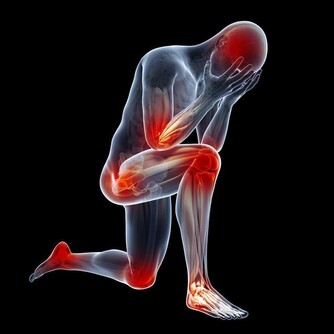

1、肺痛累及胸痛、肩背痛。當了肺癌晚期後,疼痛可以說是每個患者都會出現的症狀。大多數已發生胸內區域性播散的肺癌患者均有胸痛的症狀。肺外圍型肺癌常向後上發展,侵蝕胸膜,累及肋骨和胸壁組織,從而引起肩背痛。這類患者很少有呼吸道症狀。

2、骨關節異常。一旦肺癌疾病發展到晚期,癌細胞分泌的特殊產物就會危及骨關節。肺癌細胞可產生某些特殊的內分泌激素(異源性激素)、抗原和酶,這些物質運轉作用於骨關節部位,而致骨關節腫脹疼痛,常累及脛、腓、尺、橈等骨及關節,指趾末端往往膨大呈杵狀指,x線攝片檢查可見骨膜增生。